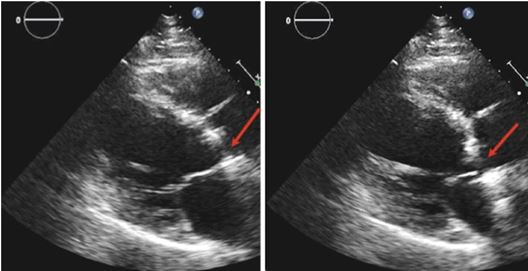

КМП Такоцубо була вперше описана близько 20 років тому в Японії як транзиторна стрес-індукована дисфункція верхівкового відділу ЛШ [38]. Ця КМП відповідає приблизно за 2% всіх пацієнтів, госпіталізованих з підозрою на ГКС. Типово це жінки (>90%) в перименопаузі, хоча цей стан може траплятися в усіх групах пацієнтів [39]. КМП Такоцубо є станом мімікрії ГКС, тому що типово пацієнти поступають з болем в грудній клітці та характерними змінами на ЕКГ, але без ангіографічних ознак ГКС [40]. Вона характеризується зворотною дисфункцією ЛШ з регіональними порушеннями скоротливості, що не повністю відповідає типовим зонам (басейнам) коронарного кровопостачання. Типовий приклад КМП Такоцубо виглядає як апікальна акінезія ЛШ (Рис. 1), що робить ЕхоКГ ідеальним діагностичним інструментом у багатьох з таких пацієнтів. Втім, коронароангіографія (КАГ) при підозрі на КМП Такоцубо є обов'язковою для виключення коронарної оклюзії або значущих коронарних стенозів. Сьогодні відомо, що КМП Такоцубо має більш різноманітні клінічні прояви, ніж вважалося раніше, із залученням в зони акінезії серединних та базальних сегментів ЛШ або ПШ з або без залучення інших сегментів ЛШ. Залучення обох шлуночків описану приблизно у чверті пацієнтів [41], а залучення серединних сегментів ЛШ недавно було описано в 40% всіх випадків [42]. Для підтвердження діагнозу КМП Такоцубо необхідне повне відновлення функції ЛШ протягом лікування (термін може бути варіабельним: від декількох днів до багатьох тижнів) [43].

Рис. 1. ЕКГ, ЕхоКГ та вентрикулографія у пацієнта з гострим болем в грудях, розповсюдженим порушенням скоротливості верхівки ЛШ (стрілка) та незначним підвищенням рівня тропоніну. У пацієнта діагностовано кардіоміопатію Такоцубо після виключення значущого ураження коронарних артерій підчас КАГ.